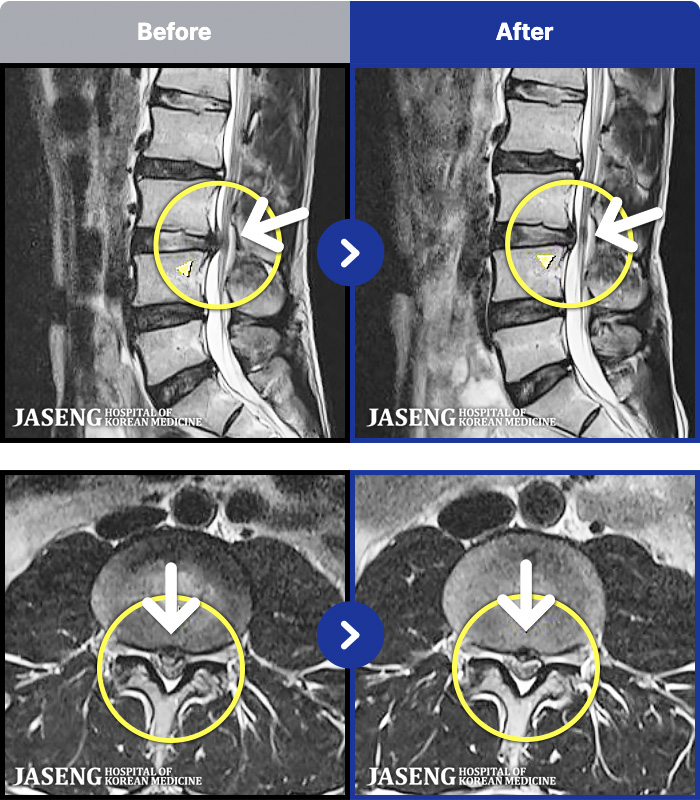

- MRI ġ

MRI ġ

97 MRI ũ ʸ Ȯϼ.